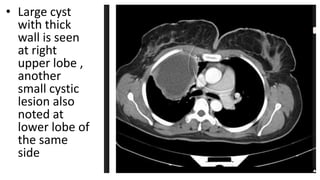

• Large cyst

with thick

wall is seen

at right

upper lobe ,

another

small cystic

lesion also

noted at

lower lobe of

the same

side

• Large cyst withthick wall is seen at right upper lobe , another small cystic lesion also noted at lower lobe of the same side